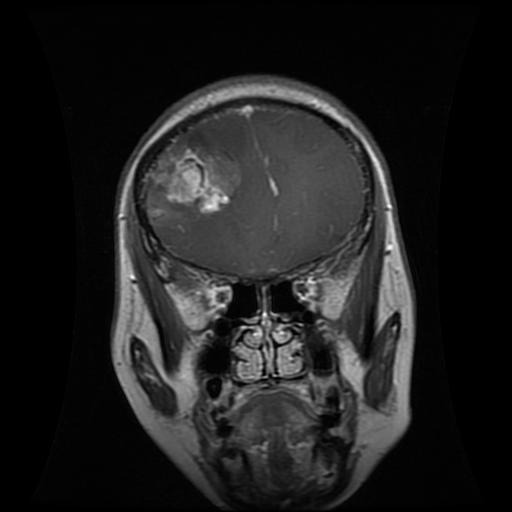

Figure 1: Samples of Glioma segmentation across different imaging planes

Glioma: Gliomas are irregularly shaped and often infiltrate surrounding tissues, presenting significant challenges for precise boundary definition. These complexities require robust segmentation techniques to capture their variable morphology. As shown in Figure 1, gliomas exhibit irregular and diffuse growth patterns, which are highlighted through annotated tumor masks.